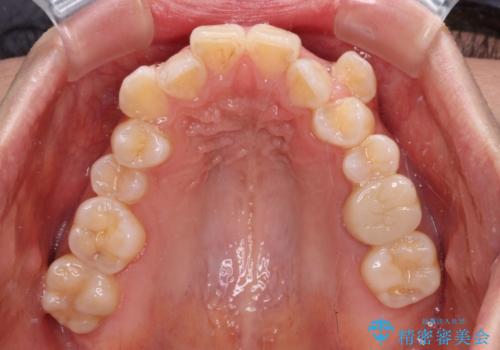

- 咬み合わない前歯と八重歯などのデコボコを気にして来院された患者様です。

上下前歯の位置を比較すると上顎が前方にあり、デコボコ改善でより上顎が前方に行く可能性があります。

開咬の改善にはインビザラインが有効であり、インビザライン単体での治療を検討しましたが、上顎前突を回避するために上顎左側第一小臼歯抜歯を行うこととしたため、補助装置とワイヤー矯正を併用した上で、インビザラインによる矯正治療を行うこととしました。

インビザライン矯正治療では、臼歯の圧下による前歯部の早期接触が大きな問題となっています。開咬では、その臼歯圧下を逆手にとって前歯部の非接触を改善させることができます。